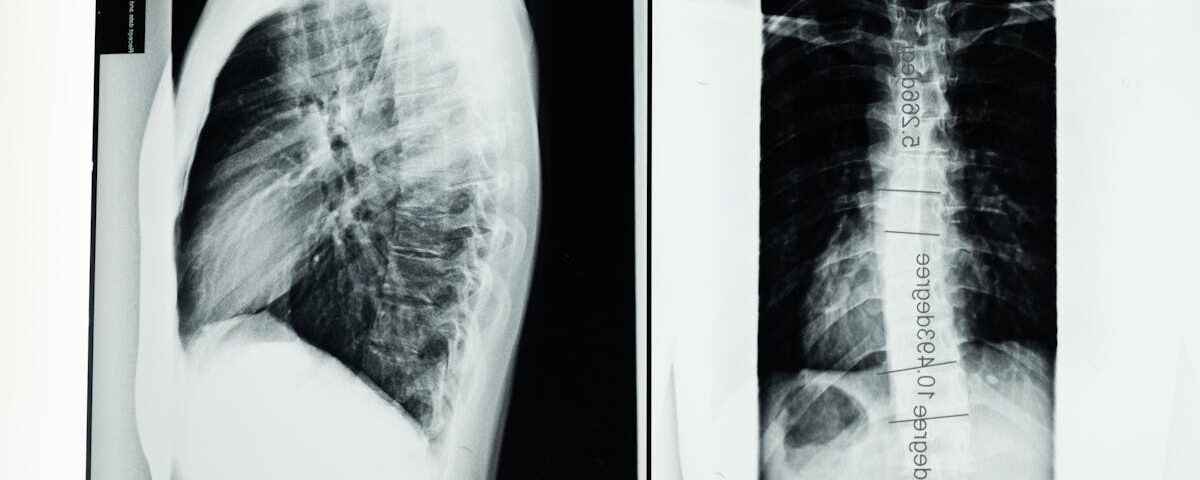

Quels examens sont nécessaires avant de commencer un traitement de décompression?

Une IRM ou une radiographie est généralement nécessaire pour évaluer l’état de la colonne vertébrale.

Quels examens permettent de diagnostiquer une hernie discale?

Une IRM ou une radiographie est utilisée pour confirmer le diagnostic d’une hernie discale.